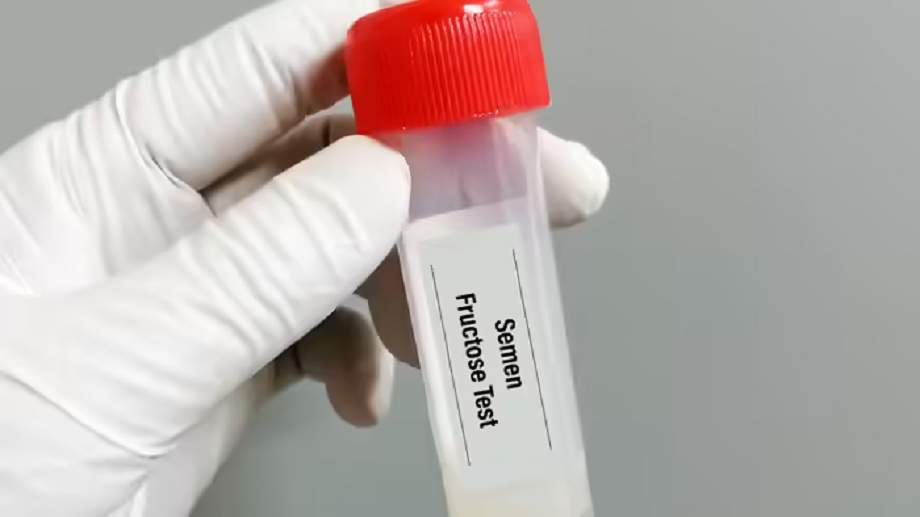

After the death of her partner, a woman resorted to a unique technique known as the PSMR (Pmsr) technique to conceive. Let's learn what this technique is and how it works.

To achieve pregnancy after the Captain's death, Dr. Levy used postmortem sperm retrieval (PSR). According to media reports, he even obtained legal permission to use his partner's sperm for this procedure.

According to the National Library of Medicine, postmortem sperm retrieval (PMSR) is a medical procedure that extracts live sperm from a deceased man for later use in assisted reproductive therapy (ART). This procedure then allows a woman to conceive through IVF.

The National Library of Medicine reports that the first PMSR case was reported in 1980. Since then, numerous cases have been reported in which women have become pregnant and delivered babies using PMSR. Requests for and use of this procedure are increasing in the United States, but the technique remains controversial.

According to the American Society for Reproductive Medicine, it is ethically justifiable to extract or use sperm or eggs after death for reproductive purposes , provided the deceased person's written permission is available. If such written permission is not available, the use of sperm, eggs, or embryos after death should only be considered if the request comes from the deceased's spouse or partner.